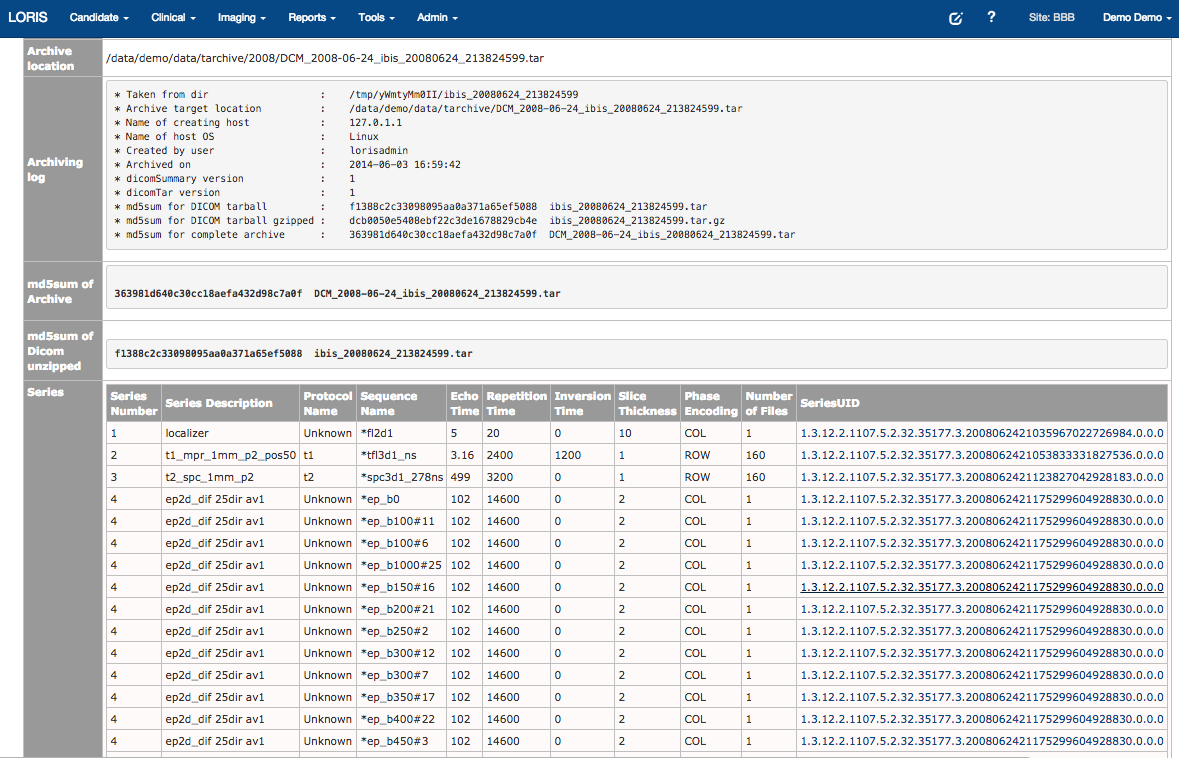

DICOM archives

Raw data can be accessed (e.g. DICOM archiver)